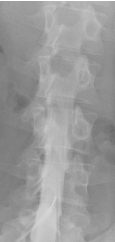

Die Myelographie ist ein invasives Verfahren an der Wirbelsäule. In der Neuroradiologie Heidelberg führen wir eine Myelographie jeweils nur zur weiterführenden bildgebenden Diagnostik bei Engen des Wirbelkanals oder der Nervenaustrittskanäle durch – also erst dann, wenn durch reguläre MRT- oder CT-Bildern nicht genaue Ergebnisse geliefert werden konnten. Vergleichen Sie hierzu unser gezeigtes Beispiel: